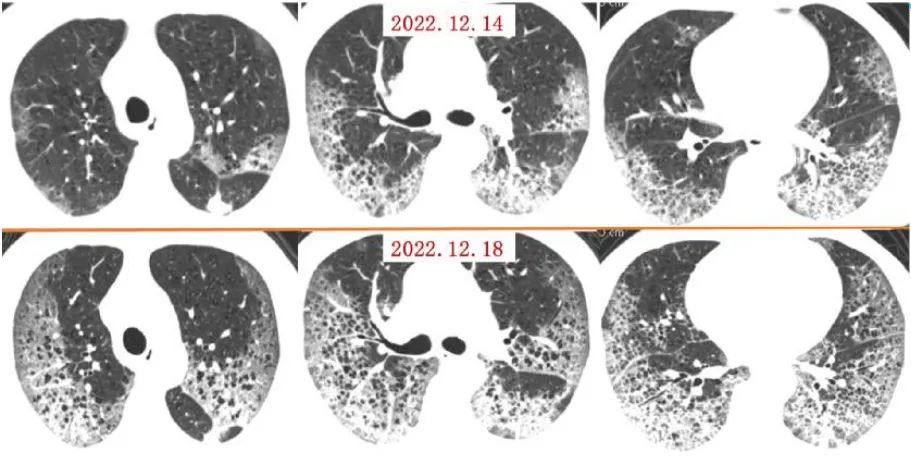

案例一,61歲,女性,確診病例

胸片顯示整個雙肺已經(jīng)白化

影像所見:有慢性阻塞性肺疾病病史。2周前受涼后出現(xiàn)發(fā)熱,伴咳嗽、咳痰。入院后給予吸氧,5天后出現(xiàn)口唇紫紺 ,改為BIPAP呼吸機(jī)輔助通氣。12月14日和12月18日,兩肺病灶自肺野外周、下后部向中心和上部迅速擴(kuò)展,表現(xiàn)為“白肺”。